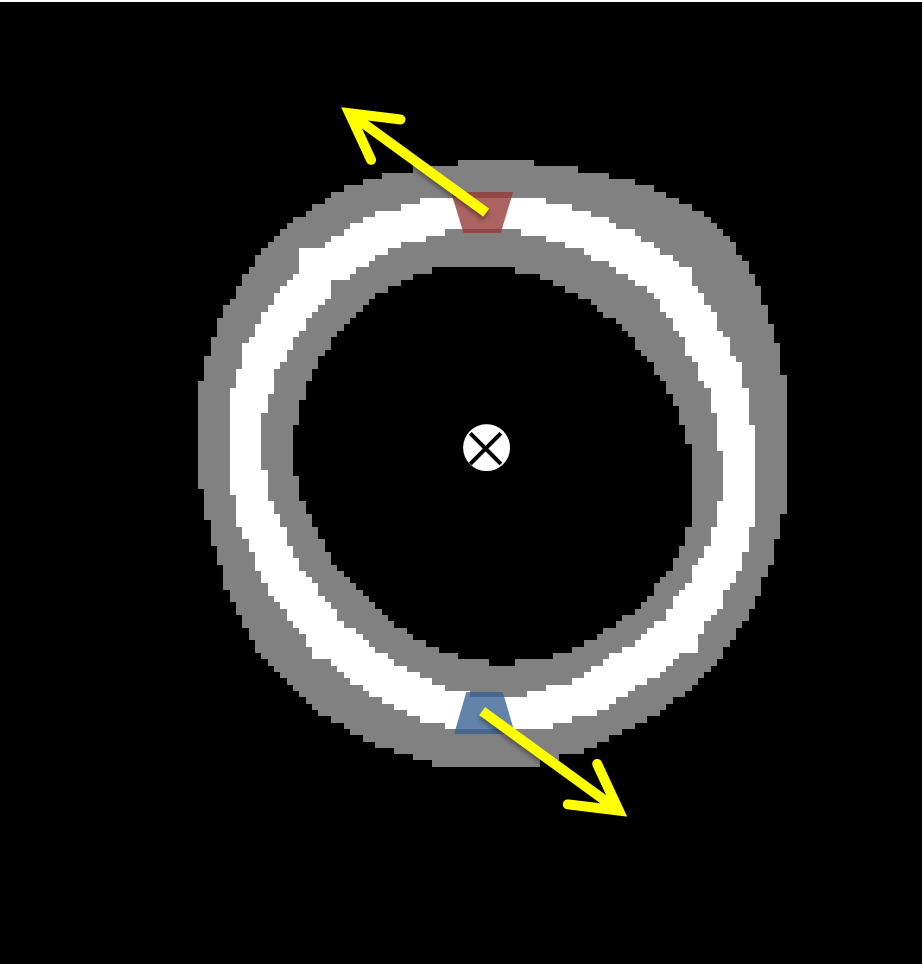

In a LV model of the shape of a perfect hollow truncated ellipsoid, the region of integration (ROI) is defined as a subregion of the LV of similar shape and smaller width aligned with the LV short axis. The cross sections of this region with the slice planes are rings of various radii and constant width. It is important that the ROI is equi-width and equidistant from the LV endocardial and epicardial surfaces in order that the error in integration is minimum. To take into consideration variations of the real LV shape from this LV shape model, the ROI is adjusted to another equiwidth and equidistant region sitting in the LV wall. This region is formed by closed straps around the medial axis of the LV cross sections on each slice, which are extended along the longitudinal direction. The closed straps (also called rings in this work), are computed as the dilated skeleton of the myocardial mask on each slice.

Consider a ring (ROI) from the Z-th slice of a real dataset with area S, as shown in Fig.1. Let (in blue, Fig.1a) and (in red, Fig.1a)be two infinitesimal segments of that are symmetric about the centre. Then and , where is the constant width of the ring by definition and , are the circumferential infinitesimal lengths of and respectively. Because there is neglegable varitation of the mask along the circumference of the ring, it can be considered that , hence . If and are the velocities at and respectively and model A symmetry applies, and thus or . Integrating the latest relationship, it is proved that , for each slice. If ROI is defined in the 3D space .